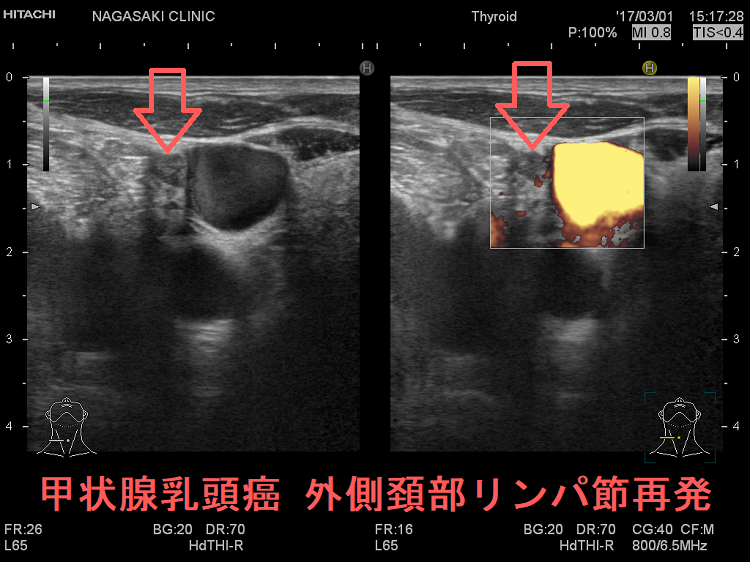

甲状腺乳頭癌 外側頚部リンパ節再発 超音波(エコー)画像

甲状腺乳頭癌 外側頚部リンパ節再発 超音波(エコー)画像 (拡大)

甲状腺乳頭癌 外側頚部リンパ節再発 超音波ドプラー画像 (拡大)